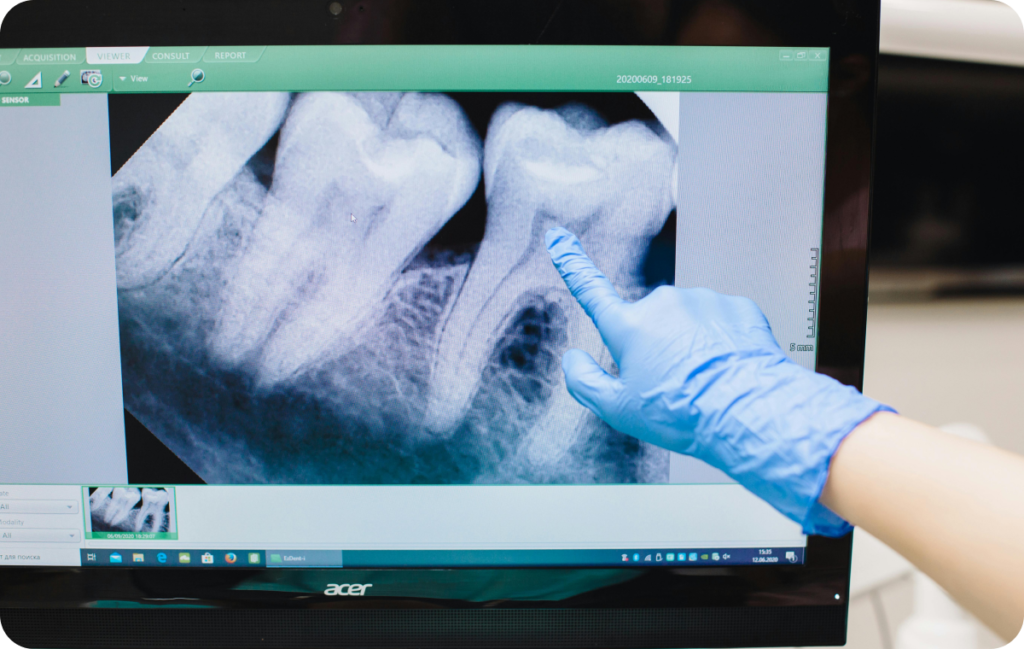

Diagnostic et radiographie à Paris 17

Avant de commencer, le praticien examine la dent. Ensuite, il réalise une radiographie. Ainsi, il peut voir la forme des racines et la présence d’une infection autour de la dent. Cette étape est importante car chaque dent possède une anatomie différente. De plus, elle permet d’évaluer la difficulté du traitement.